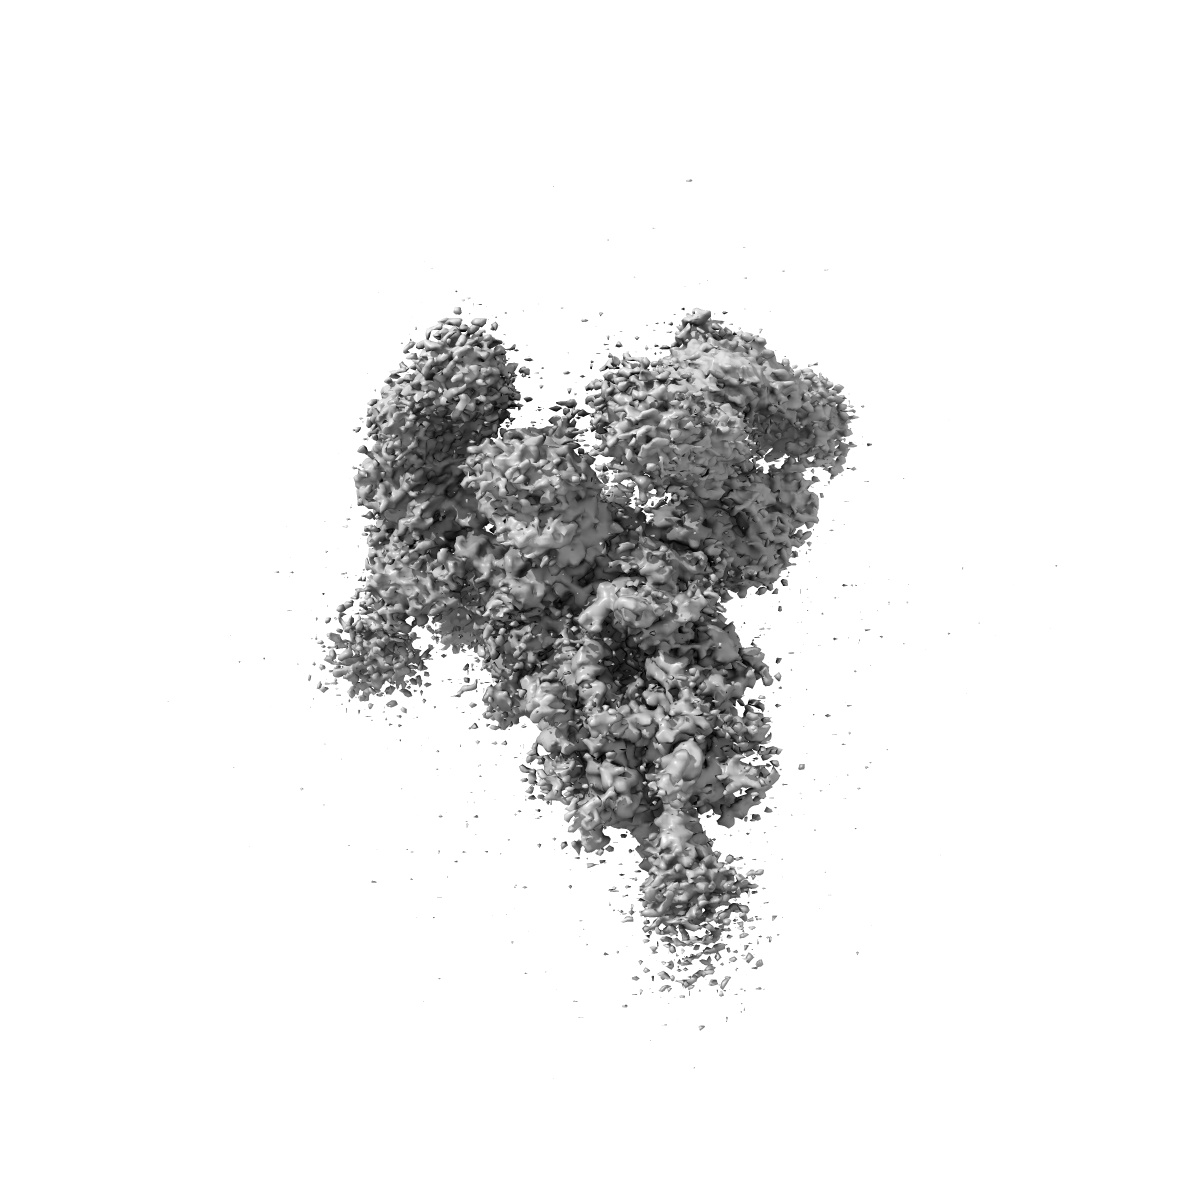

SARS-CoV-2 spike trimer (6P) in complex with two H18 and two R1-32 Fabs

Single-particle3.96 Å

Sample: SARS-CoV-2 spike trimer (6P) in complex with two H18 and two R1-32 Fabs